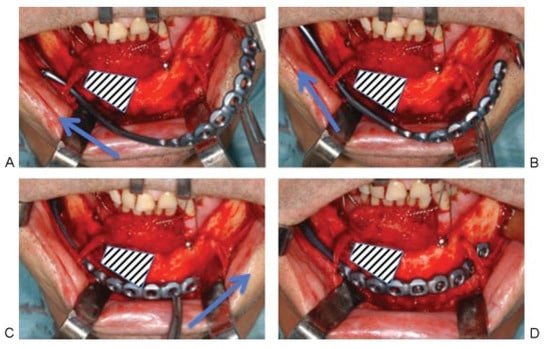

In a bilateral crossway situation the aluminum template reaches over a hemimandible and the parasymphysis into the contralateral body region. First, the template underpasses the nerve loop within the anterolateral defect/fracture zone and is then moved further backward under upward rotation of its posterior end to bring the anterior plate end into a midline position. Second, the plate is slid forward again to thread the anterior plate end underneath the opposite nerve loop on its passage to the body region (Figure 3).

Figure 3. Bilateral crossway situation with a defect area at the right parasymphyseal region. (A) MMPRP is threaded underneath the ipsilateral (right) mental nerve loop. The arrow indicates the initial backward movement of the posterior plate end. (B) The plate is moved further backward (arrow) under upward rotation of its posterior end. (C) After the anterior plate end nearly reaches a midline position, the plate is slid forward again to thread the anterior plate end underneath the contralateral (left) nerve loop (arrow) on its passage to the body region. (D) MMPRP [Synthes Maxillofacial, Paoli, PA] in its final position, reaching from posterior margin of the ipsilateral ramus into the contralateral body region.